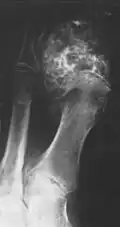

Das Chondrosarkom ist der zweithäufigste bösartige Knochentumor. Sein Auftreten nimmt mit dem Alter zu und erreicht um das 6. Lebensjahrzehnt seinen Gipfel. Es sind mehr Männer als Frauen betroffen. Bevorzugt tritt der Tumor in den Beckenknochen und am rumpfnahen Femur auf.[1]